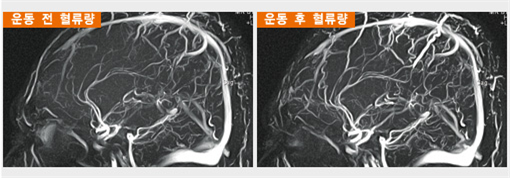

당연하겠지만 운동은 뇌 속의 혈류량을 증가시킨다. 운동을 하고 뇌혈관을 관찰하면 보다 세밀하고 뚜렷하게 관찰되고 뇌로 가는 혈액의 양도 늘어나게 된다. 또 운동은 집중력과 침착성을 높이고 충동성을 낮춰 우울증 치료제인 프로작이나 리타린을 복용하는 효과가 있다. 운동을 하면 행복감을 만드는 세로토닌뿐만 아니라 활력, 동기부여, 행동조절에 관여하는 도파민을 증가시키기 때문이다.

noname02.png <과천의과대학 뇌과학연구소 사진>